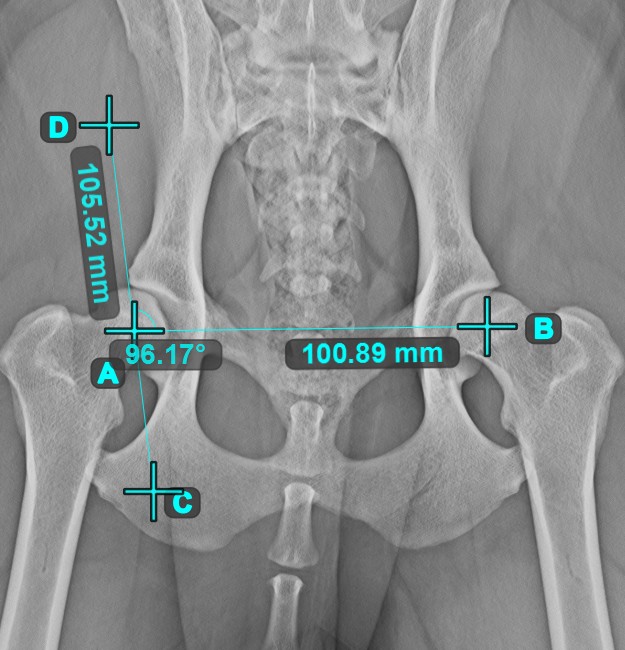

Calculate the angle between two independent or intersecting lines by using the Angle of Lines tool.

Select the tool from the left toolbar and assign it to one of the available mouse buttons. Start by selecting the first line from the ones already drawn on the scene, or place the start and end points to create the line. Follow the same steps for the second line of the measurement. The angle between the two lines will be automatically calculated.

Modify the start and end points of both lines by using the Select/Move Item tool. The angle between the two lines will be automatically recalculated.

Information

If two lines do not intersect directly, the angle of their extended projections on the scene will be calculated.

../_images/image7.jpg ../_images/image312.jpg